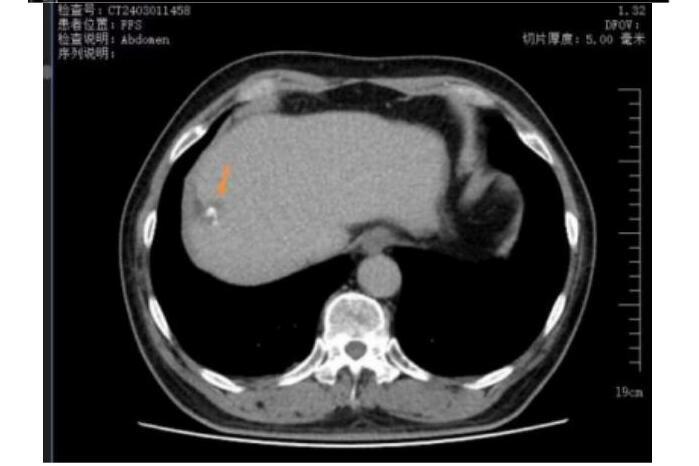

TACE联合冷冻消融

三个月复查图像 肿瘤完全灭活